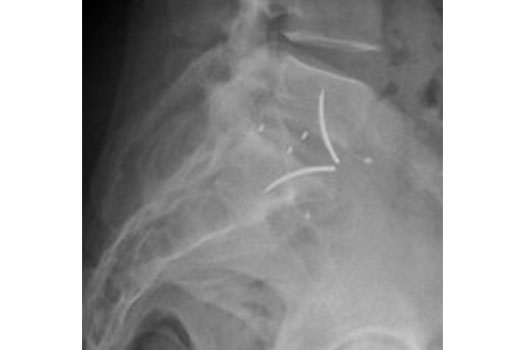

Scolioses

Généralités

Les scolioses de l'enfant (juvéniles)

Les scolioses de l'adolescent

Les scolioses de l'adulte